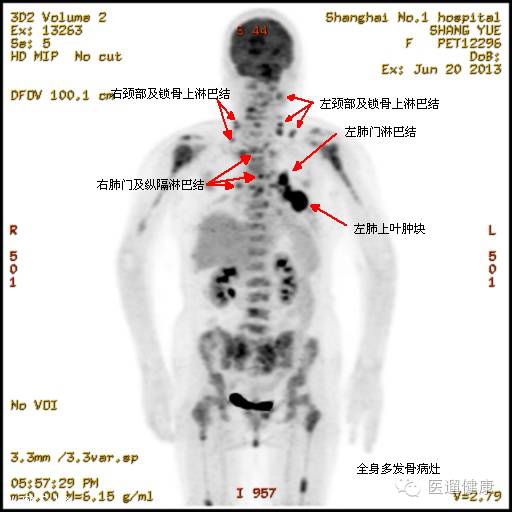

案例一、

病患:男,49岁,“吞咽困难2月余”,做了胃镜后发现食管病变。医生通过PET/CT对其食管病灶定性,了解其全身情况。

食管中段管壁不规则增厚,累及长度约5.5cm,SUV最大值22.6

我们知道SUV值越大,肿瘤的恶性程度越高。患者通过胃镜检查已经知道病变,关键是医生通过PET/CT看到了病患上纵隔有多发的淋巴结转移,肝胃韧带有多发的淋巴结转移,另外,这位病患乙状结肠上段有结节,如果只是做胸部CT的话,是不可能发现这么多的病灶的,也无法准确的分析。